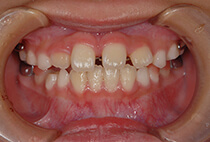

5歳6ヶ月、受け口が気になり、お母様と一緒にご来院。

「幼稚園の間に治療スタートしたい」「小学校入学時には装置に慣れた状態でいたい」とのご希望で、矯正治療をスタートしました。

治療は、急速拡大+前方牽引装置から。

1ヶ月で骨格バランスが大きく改善しました。

小学1年生の7ヶ月後には、さらにバランスの整った噛み合わせに。

成長に合わせて3回の急速拡大を行い、夜間のマウスピースとお口の機能訓練で成長をサポート。

小学生を正常なバランスで過ごすことができました。

中学校入学と同時にマウスピースを卒業し、今後は予防管理へ移行予定です。

「早めに始めてよかった」と喜んでいらっしゃいます。